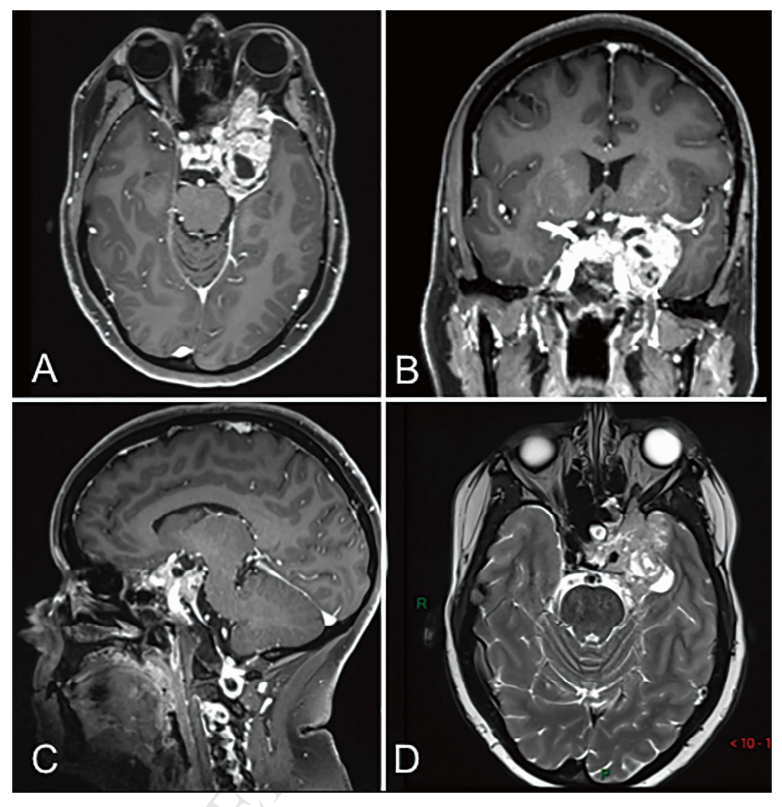

鉴于放疗后短期内即出现复发,提示肿瘤生物学行为更具侵袭性,故拟行包括海绵窦在内的肿瘤整块根治性切除。由于肿瘤已包绕颈内动脉(ICA),且左眼功能因完全性动眼神经麻痹而丧失,目标是实现安全实施海绵窦内肿瘤及全海绵窦内容的根治性切除(图1)。

图1. 术前MRI示复发性海绵窦脑膜瘤,并侵及眼眶。